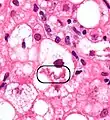

The primary characteristic of MASLD is the accumulation of lipids in the liver, largely in the form of triglycerides.[19] However, the mechanisms by which triglycerides accumulate and the reasons that accumulation can lead to liver dysfunction are complex and incompletely understood.[19][47][48] MASLD can include steatosis along with varied signs of liver injury: either lobular or portal inflammation (a form of liver injury) or ballooning degeneration. Similarly, NASH can include histological features such as portal inflammation, polymorphonuclear cell infiltrates, Mallory bodies, apoptotic bodies, clear vacuolated nuclei, microvesicular steatosis, megamitochondria, and perisinusoidal fibrosis.[16] Hepatocyte death via apoptosis or necroptosis is increased in MASH compared with simple steatosis, and inflammation is a hallmark of MASH.[32]

NASH (inflammation) and fibrosis stage 1

NASH (inflammation) and fibrosis stage 2

Lobular inflammation

NAFLD comprises two histological categories: NAFL, and the more aggressive form NASH. The presence of at least 5% fatty liver is common to both NAFL and NASH, but the features of substantial lobular inflammation and hepatocyte injuries such as ballooning or Mallory hyaline only occur in NASH. The majority of NAFL cases show minimal or no inflammation.[3][5][7] Pericentral and perisinusoidal fibrosis occur more often in adult-onset NASH, whereas portal fibrosis is more common in children with the disorder. NASH represents a more advanced stage of NAFL and is associated with poor outcomes such as cardiovascular events, cirrhosis, or hepatocellular carcinoma. ICD-11 does not use the term NAFL as it was deemed confusing with the family of disorders NAFLD. The preferred descriptions are instead: MAFLD without NASH or simple steatosis and "NASH". Also, the modifier with or without fibrosis or cirrhosis completes the diagnostic description.[3][7]